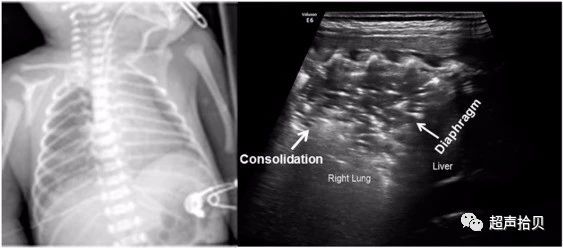

图3:新生儿肺炎的超声检查结果(胎龄31W+1 d;阴道分娩;出生体重1,550 g)在羊水胎粪污染,分娩后47小时检查。 婴儿出现呼吸窘迫,体温过低,WBC计数为19.8×109 / L,中性粒细胞为87%,血小板计数为87×109 / L。 患者机械通气,血培养生长肺炎克雷伯菌。 肺部超声显示不规则的肺实变区,右下肺大部分处有充气支气管征,胸膜线和A线消失,肺滑动消失,肺部脉搏减少。 胸部X光片显示右下肺高密度阴影;